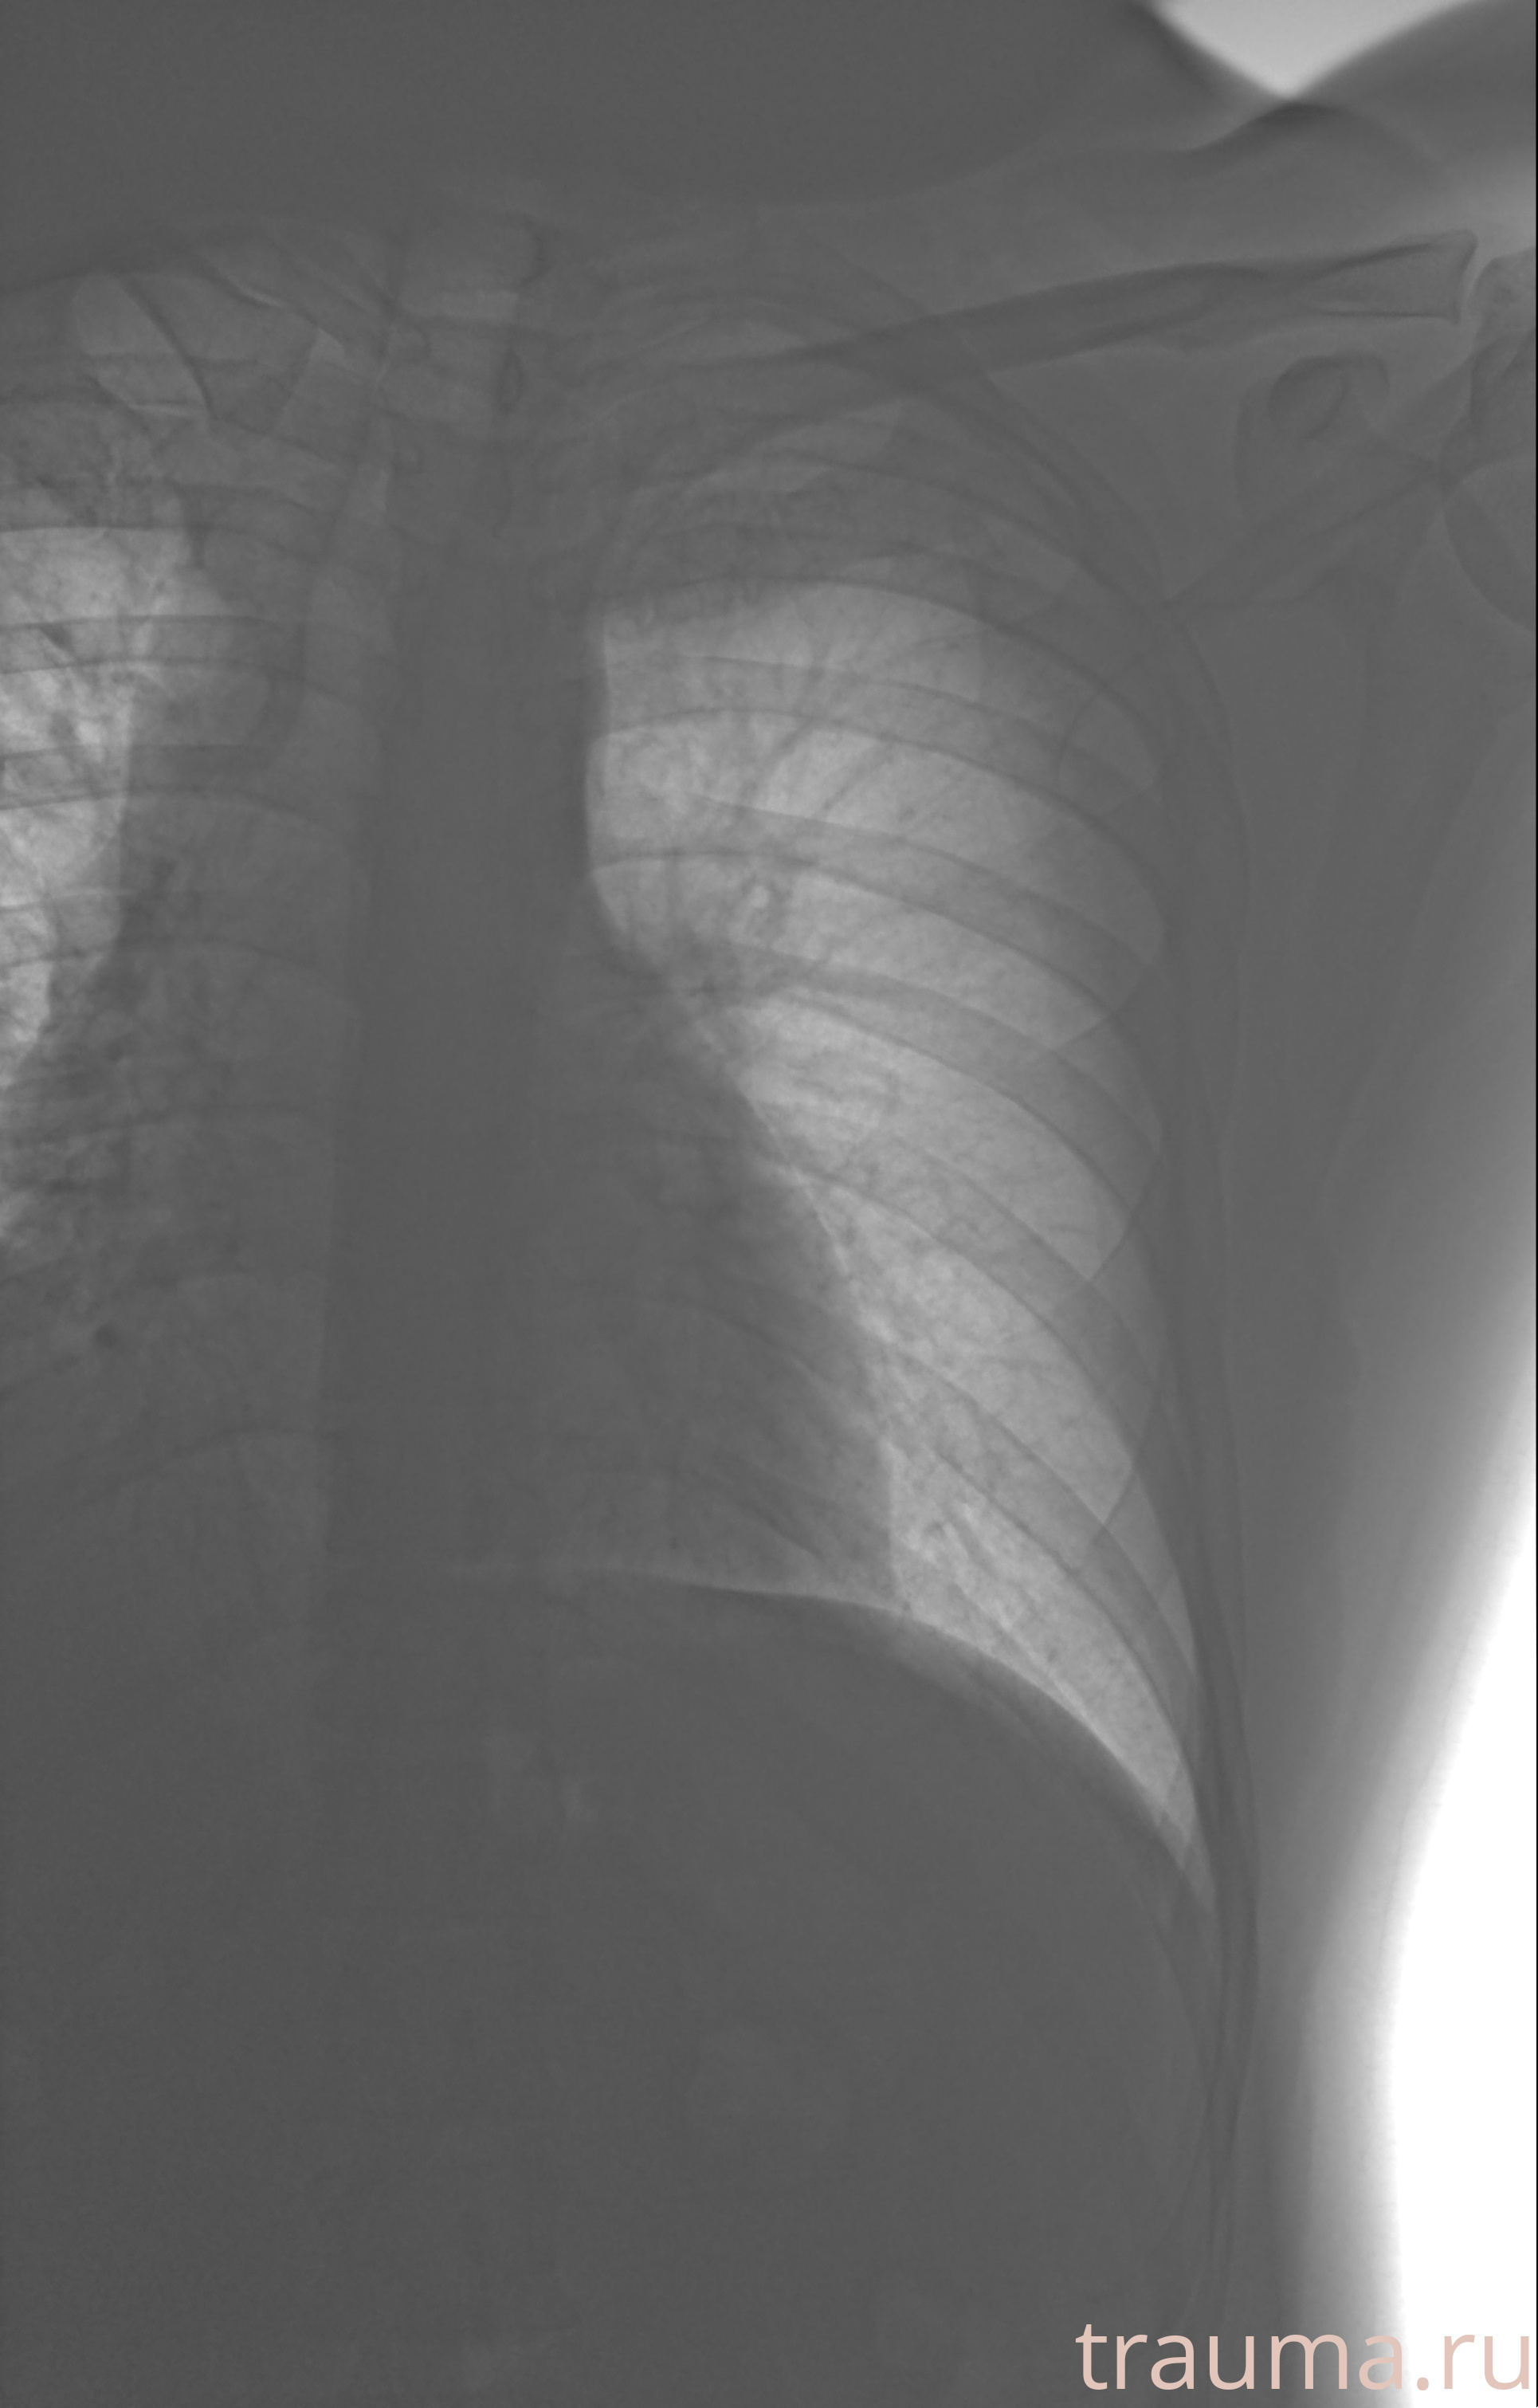

Рентгенограммы

Рентген на дому: по вашему адресу приезжает врач-рентгенолог, травматолог-ортопед с мобильным рентгеновским аппаратом, проводит диагностику травмы или заболевания, делает необходимые рентгенограммы, дает рекомендации по дальнейшему лечению. Получить качественные снимки в домашних условиях возможно благодаря уникальной методике, разработанной МосРентген Центром для института  Склифосовского